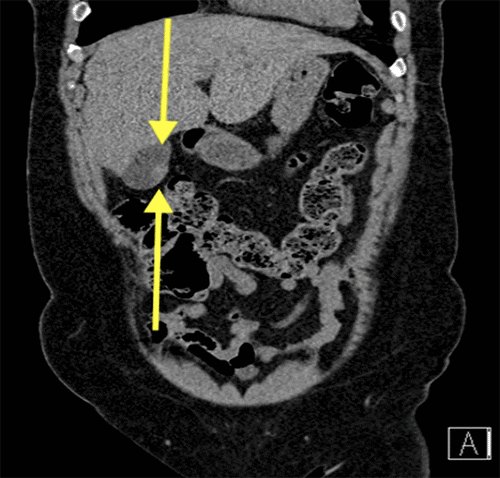

On original examination, the patient appeared well, with no abdominal tenderness, distention, guarding, masses, or evident jaundice. Initial laboratory evaluation revealed a total bilirubin of <0.2 mg/dL, alkaline phosphatase of 73 units/L, alanine aminotransferase (ALT) of 201 units/L, and aspartate aminotransferase (AST) of 290 units/L. Carcinoembryonic antigen (CEA) was elevated at 7.8 ng/mL, while CA 19-9 was within normal limits. A complete blood count and complete metabolic panel were unremarkable. Initial CT of the abdomen and pelvis demonstrated focal thickening of the gallbladder wall without pericholecystic stranding (Figure 1).

Figure 1. Abdominopelvic CT Imaging. Published with Permission

(A) Axial CT image demonstrating focal thickening of the gallbladder wall without pericholecystic stranding

(B) Coronal CT image demonstrating focal thickening of the gallbladder wall without pericholecystic stranding